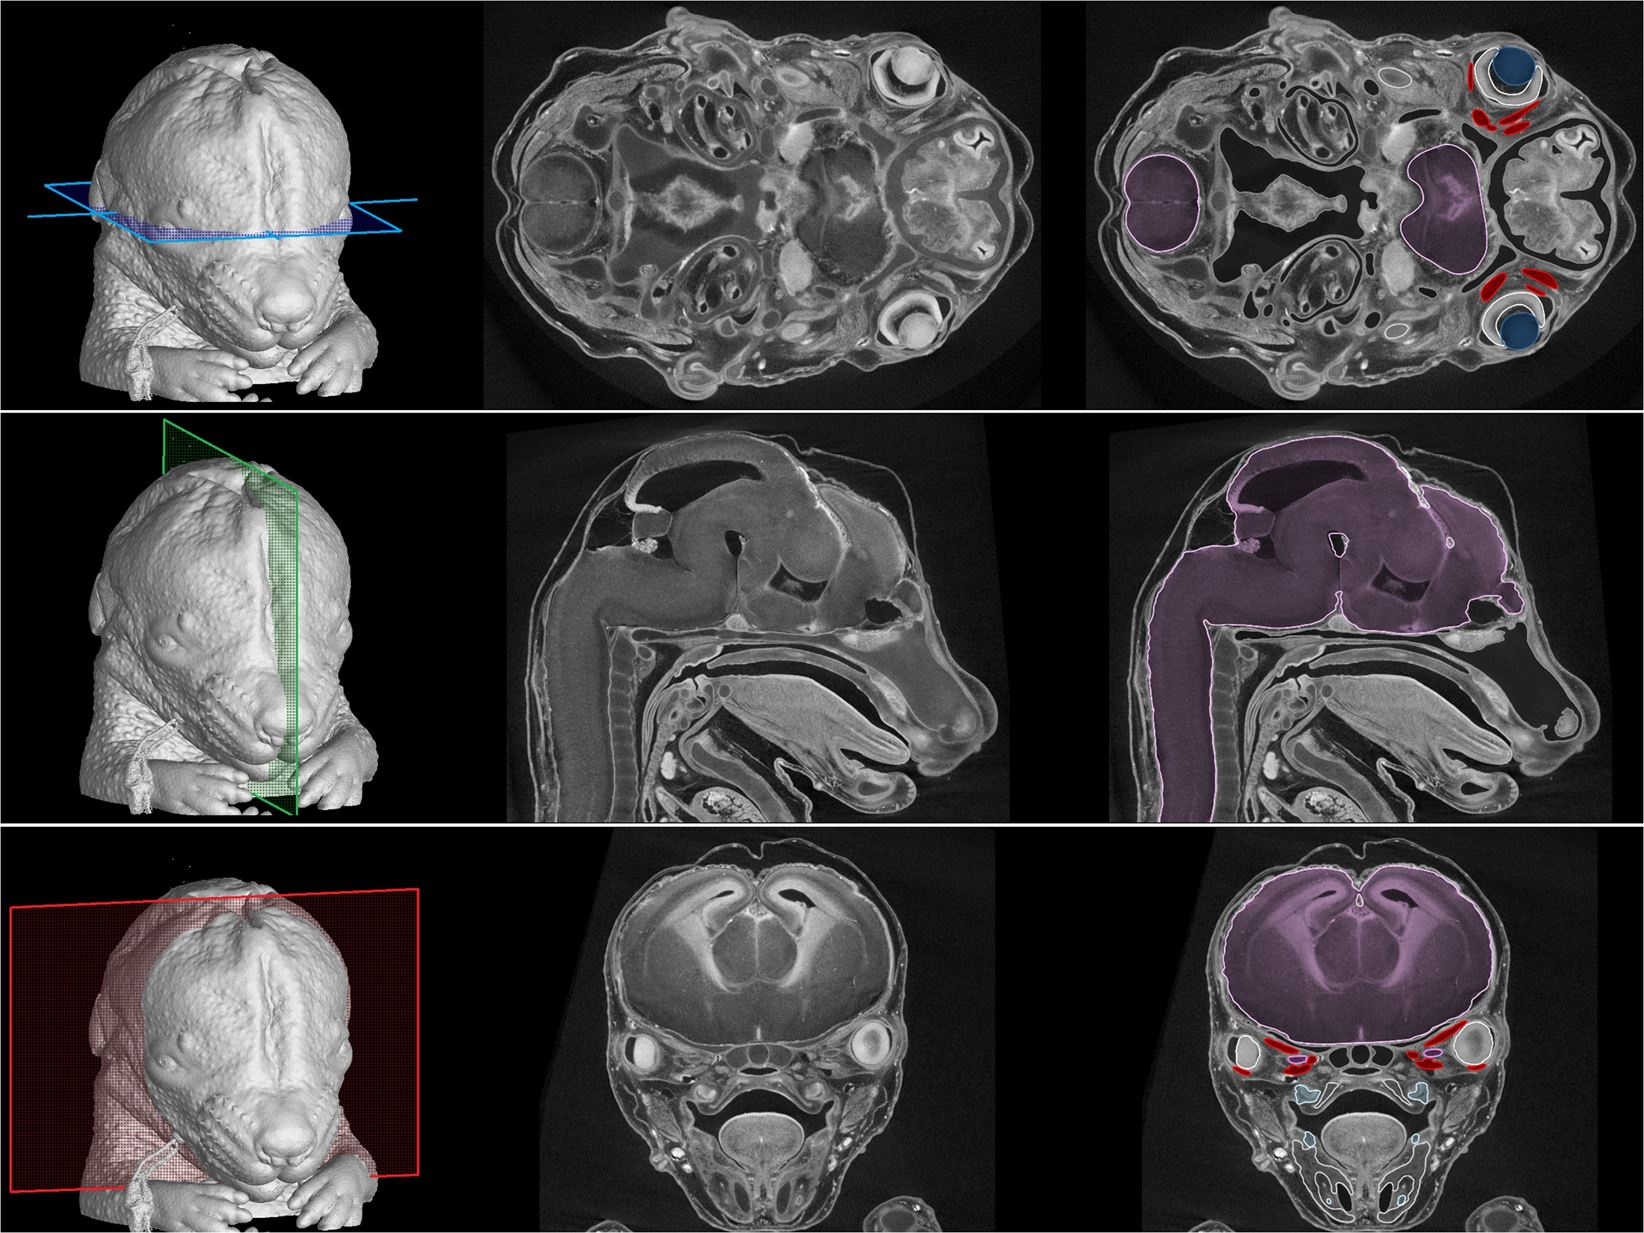

Figure 2

Tomographic measurements and segmentation of craniofacial structures in a mouse embryo 15 days post-fertilisation. Colour planes on 3D models (left panels) indicate the position of the raw tomographic slices (middle panels) and some segmented structures (right panels) including the central nervous system (purple), the lens (dark blue), the dental placodes (light blue) and extraocular muscles (red).